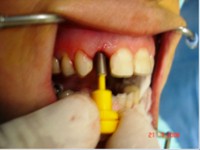

- Extração imediata

- Implante imediato

- Carga imediata